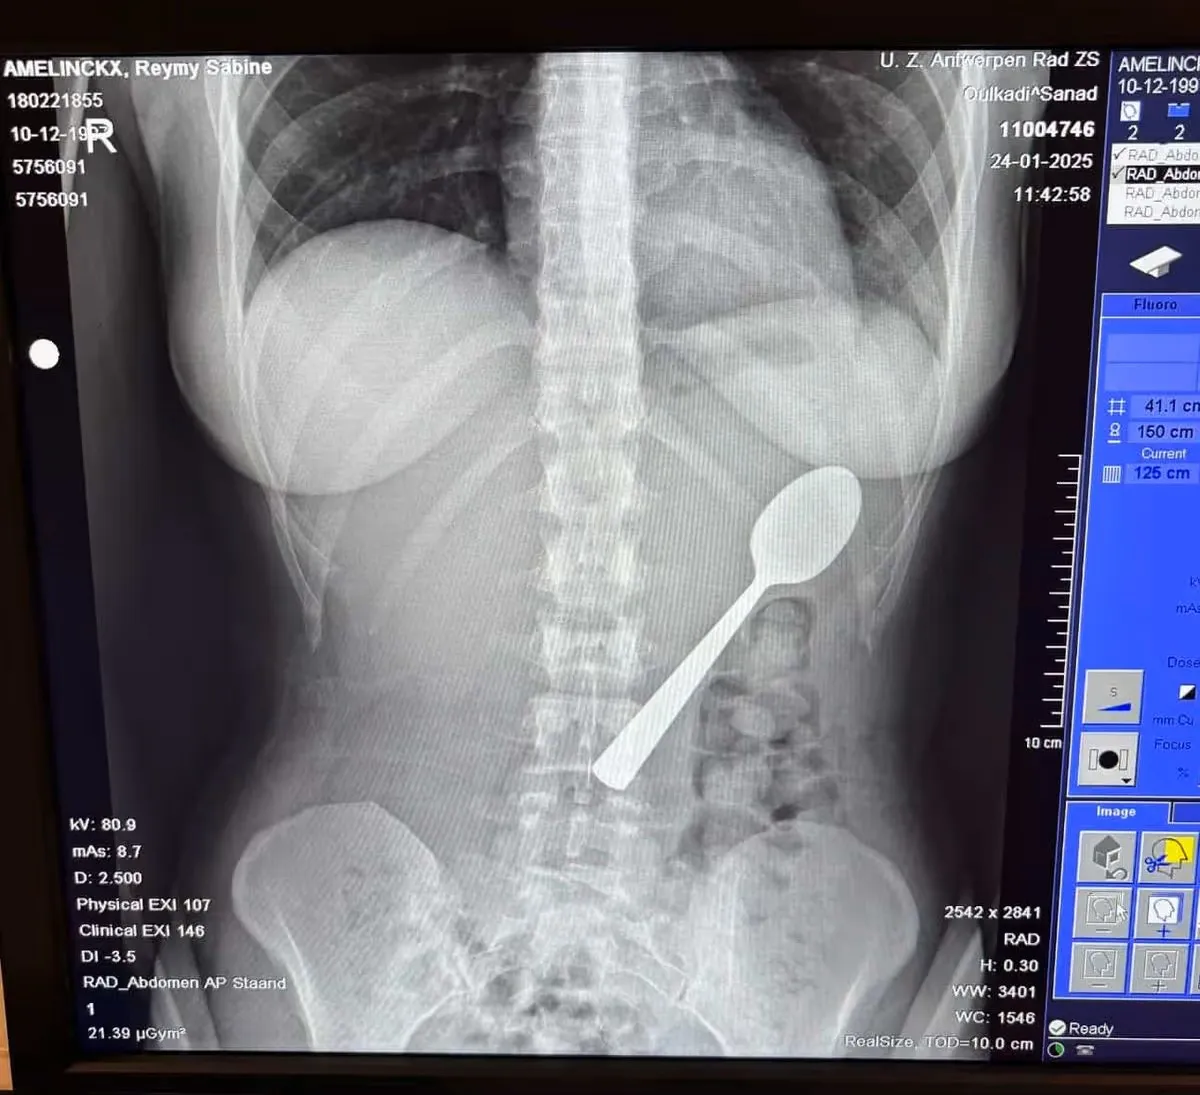

Ложка на рентгені. Фото: Mirror